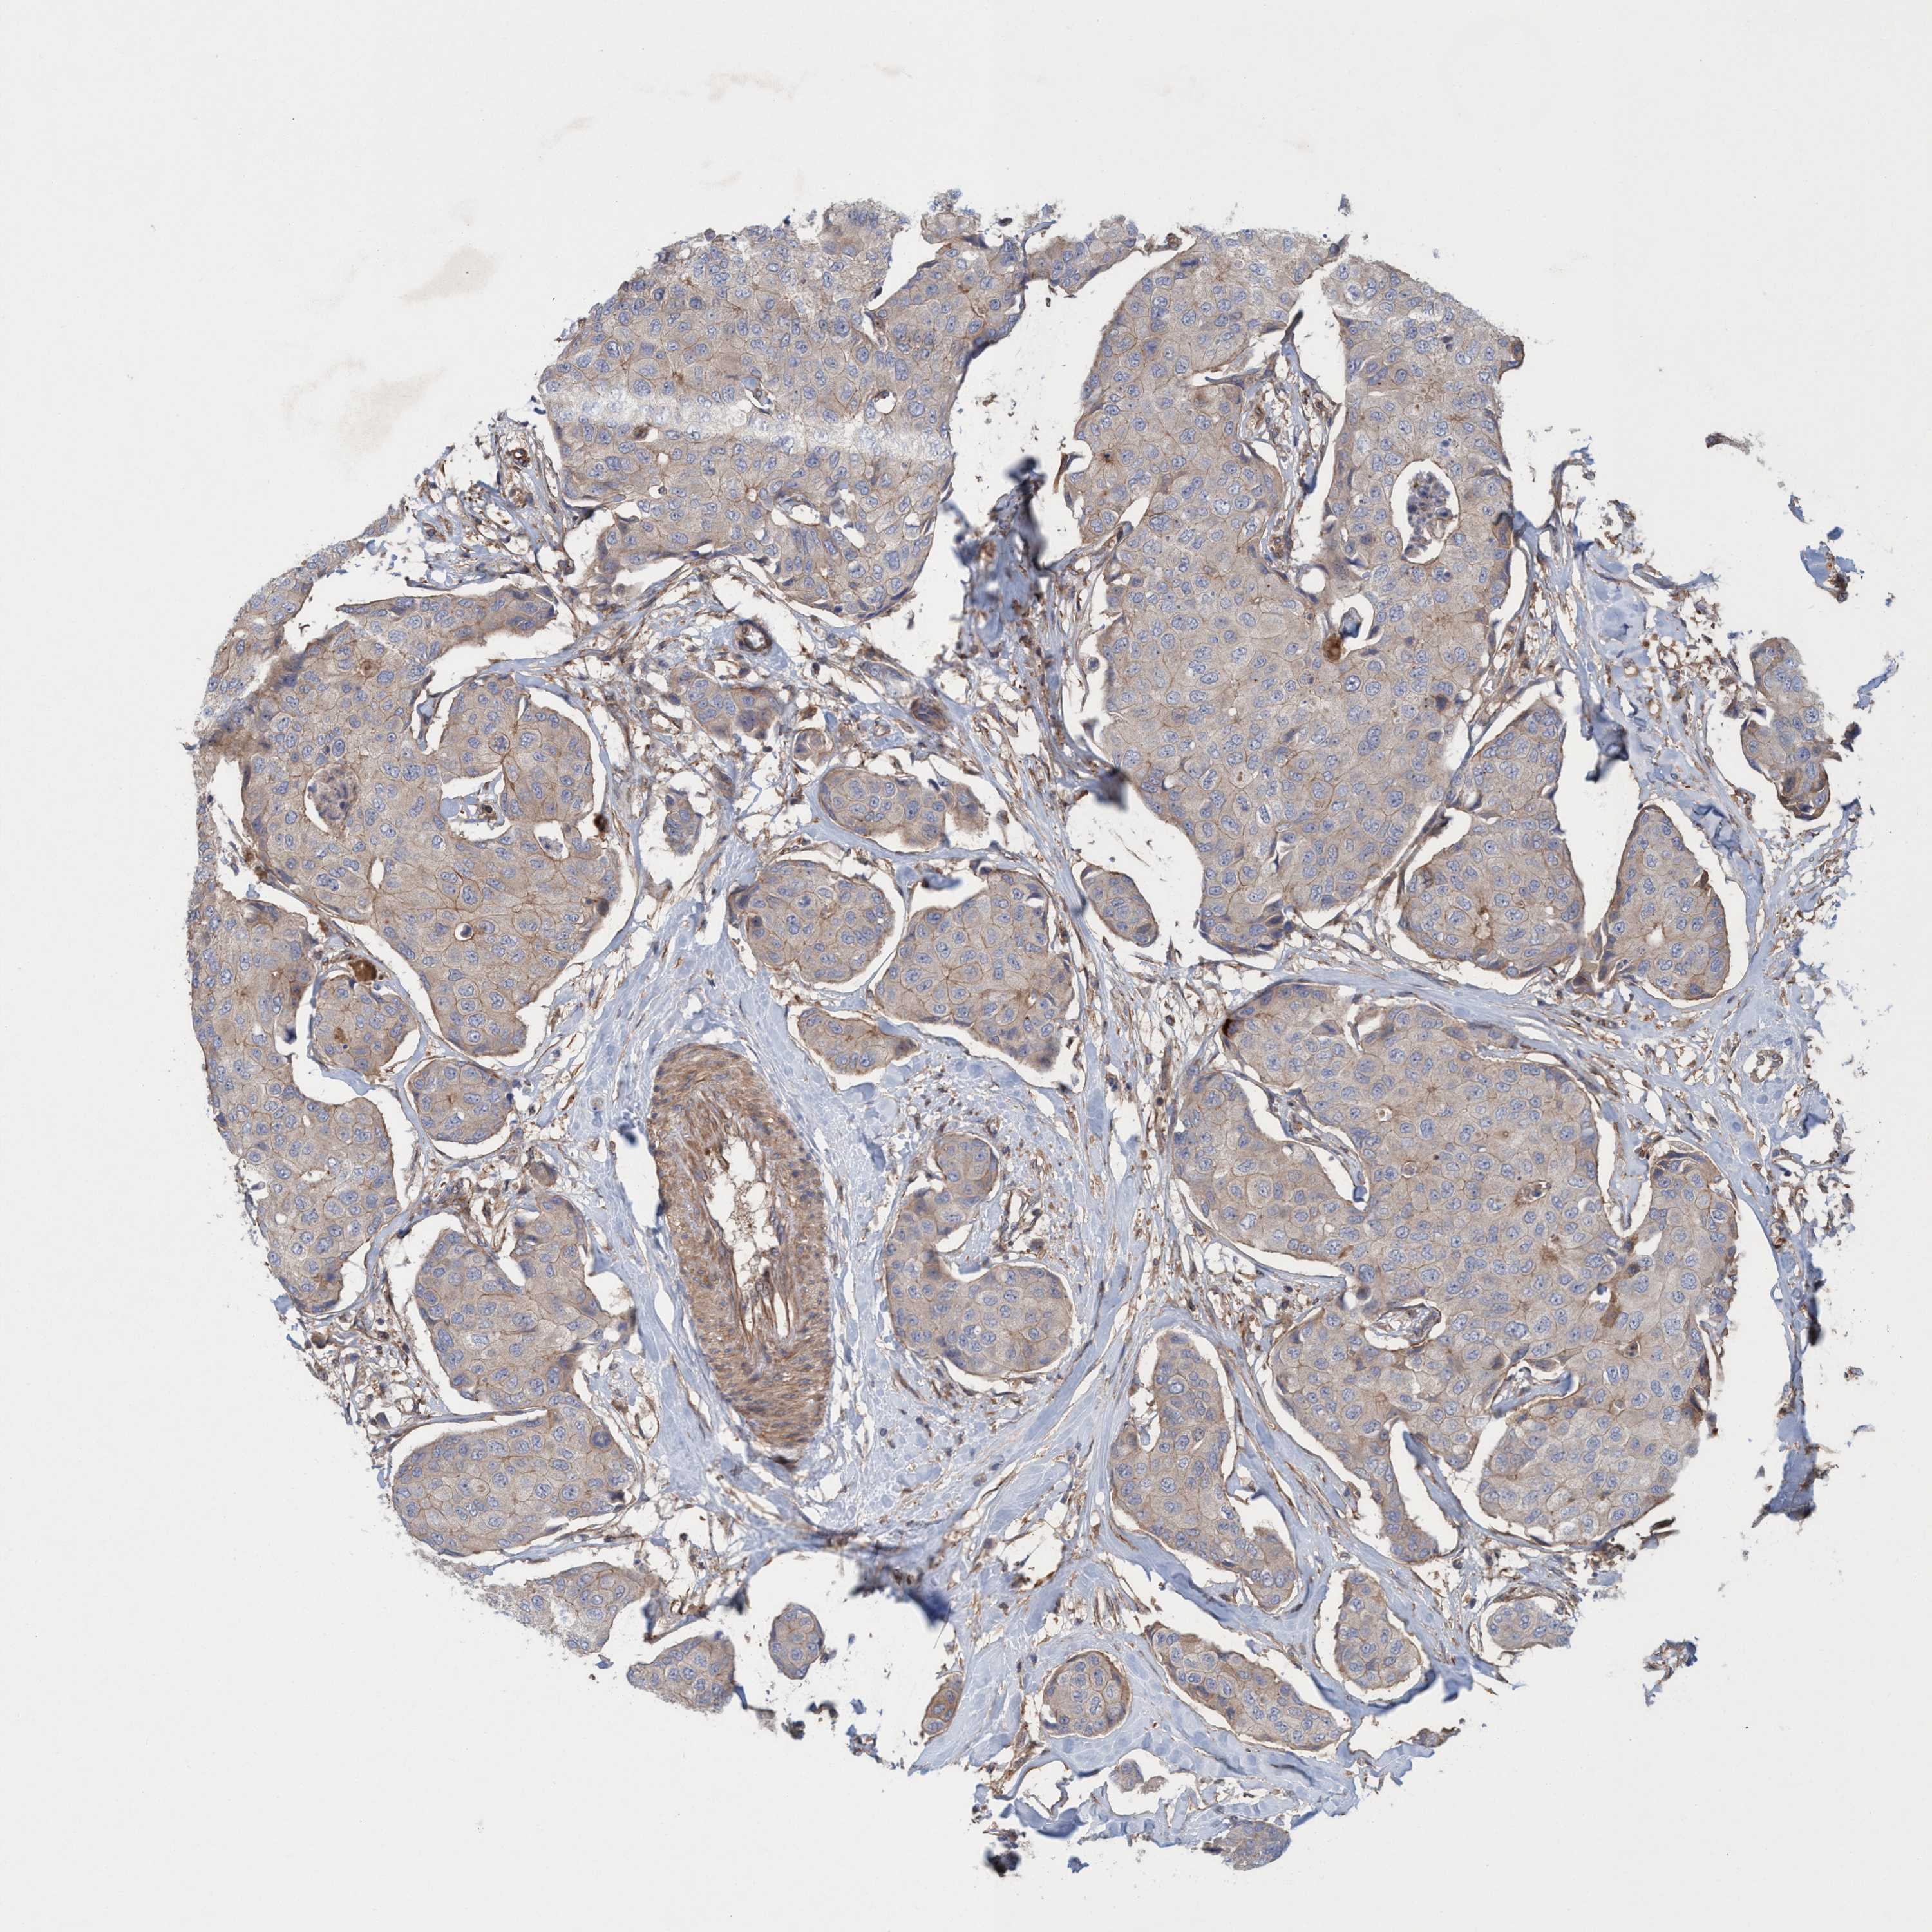

CANCER BREAST CANCER Show tissue menu

BRCA TCGA BRCA VALIDATION PROTEIN EXPRESSION